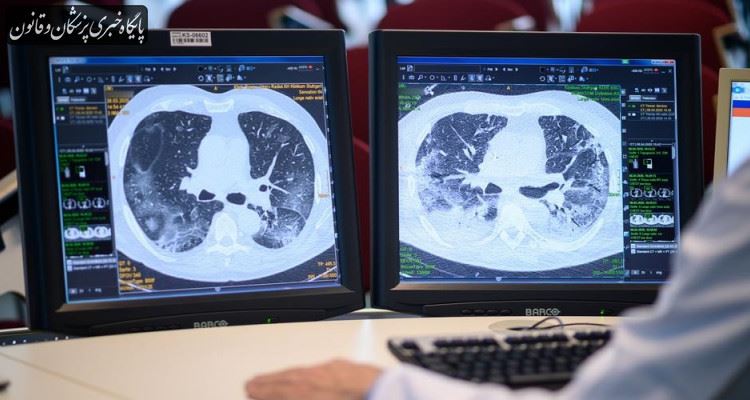

یک متخصص بیماریهای عفونی گفت: ویروس کرونا جهشهای متفاوتی داشته و سیر بالینی آن دچار تغییرات شده است اما این به آن معنی نیست که برای خارج شدن از نگرانی به انجام سی تی اسکنهای مکرر بپردازیم بلکه تنها با توجه به برخی از علائم میتوان به درگیر بودن یا نبودن ریه پی برد، برای مثال تبی که با مصرف استامینوفن کاهش پیدا میکند و مجدد اوج میگیرد، در این حالت یعنی فرد احتمال پیشرفت بیماری و درگیری را دارد، تنگی نفس و سرفههای پیشرفته با وجود مصرف داروها از دیگر علائم درگیری ریه است، همچنین ضعفهای شدید جسمانی میتواند از جمله این علائم باشد بنابراین در چنین شرایطی فرد نیاز به سی تیاسکن دارد.